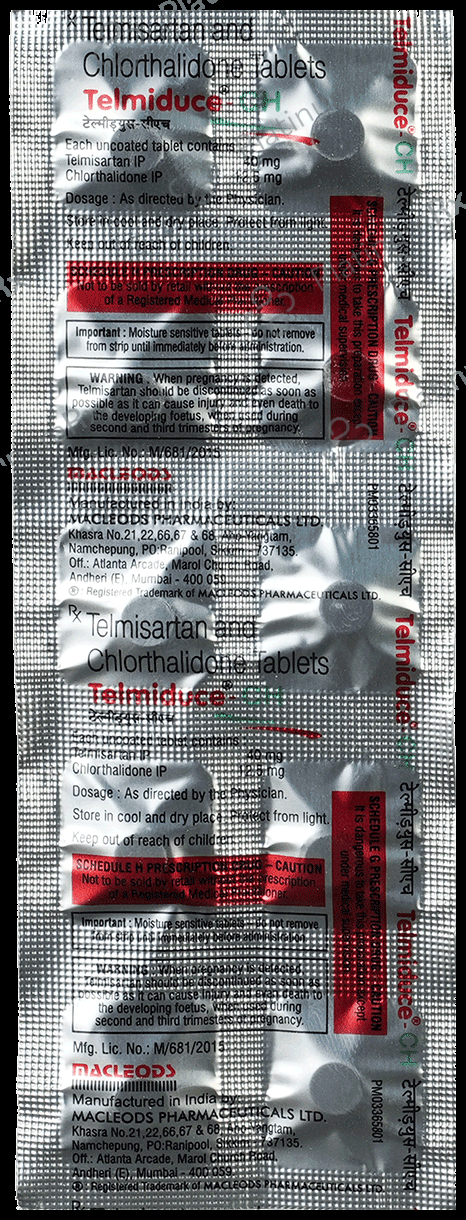

Chlorthalidone 12.5mg + Telmisartan 40mg

Salt CompositionChlorthalidone 12.5mg + Telmisartan 40mg (same for both)

Telmiduce CH 40mg/12.5mg Tablet

Telmiduce CH 40mg/12.5mg Tablet